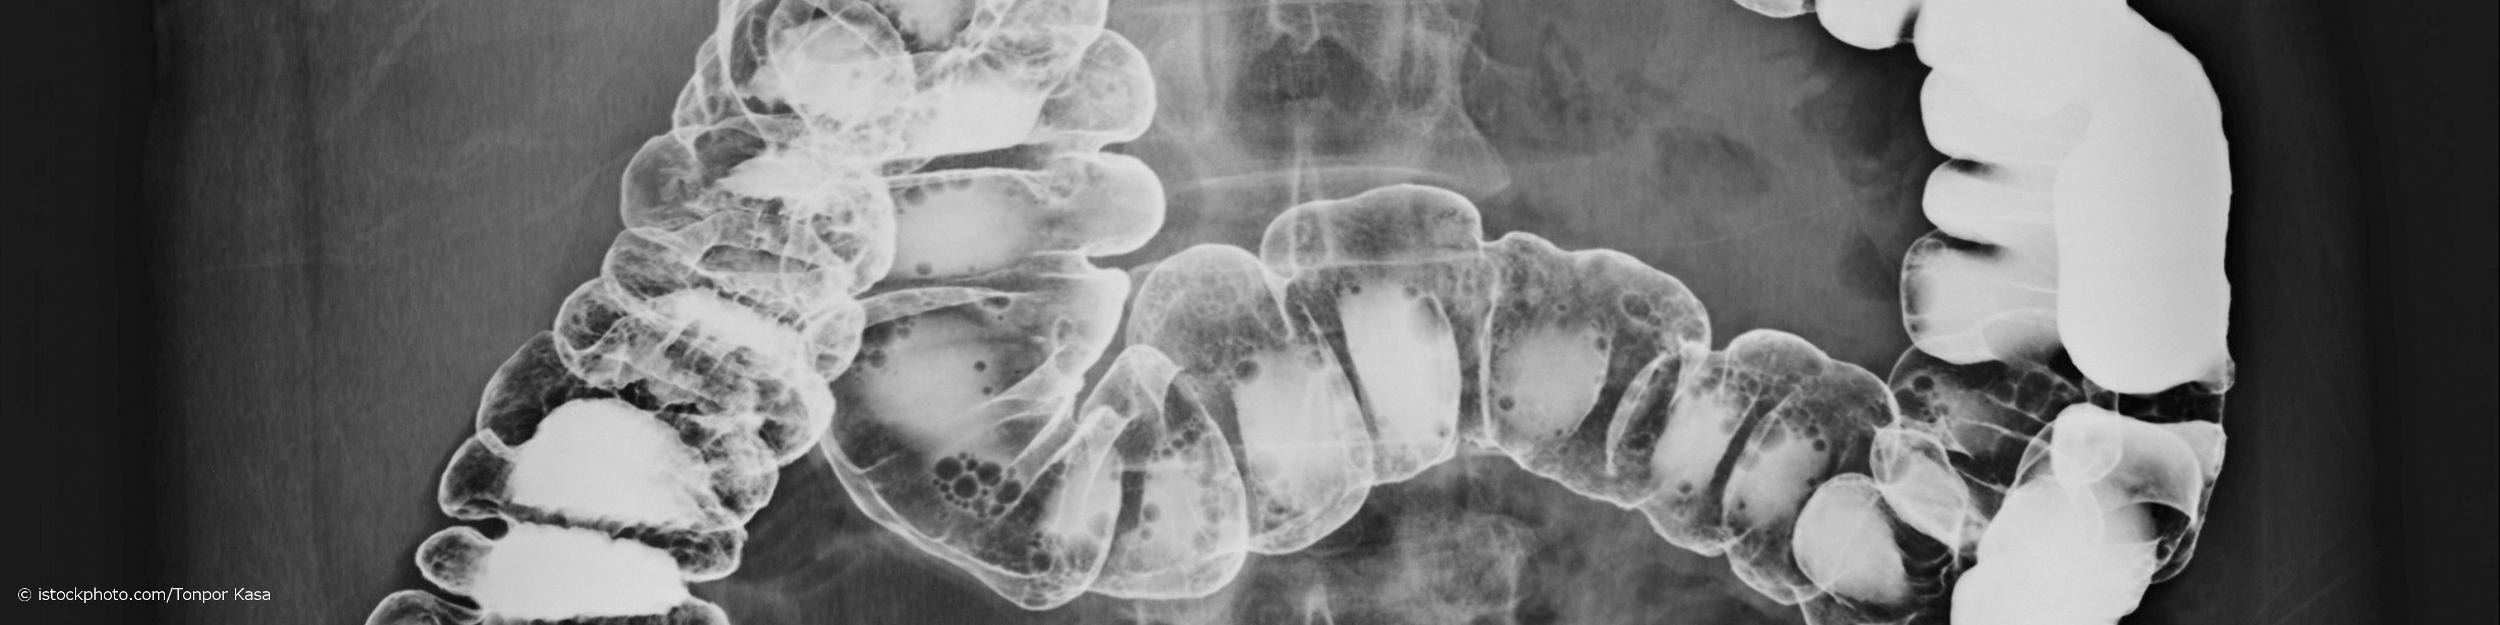

Kontrasteinlauf: Was ist das?

Die Kontrastmitteldarstellung des Kolons, auch Kontrasteinlauf (KE), Kolon-Kontrasteinlauf, Colon-Kontrasteinlauf, Kolonkontrasteinlauf, Colonkontrasteinlauf, Kolon-KE, Colon-KE, Barium Enema genannt, ist eine durch Kontrastmittel unterstützte Röntgenaufnahme des Dickdarms (Kolon). Der Kontrasteinlauf wird unter anderem bei der Diagnostik entzündlicher Darmerkrankungen eingesetzt. Da stark entzündete Darmabschnitte, stark verengte (stenotisierte) Darmbereiche oder gewundene Darmschlingen bei einer Darmspiegelung (Koloskopie) mit einem Endoskop (Koloskop) oft nicht ausreichend einsehbar sind oder nicht überwunden werden können, stellt der Kontrasteinlauf eine alternative Untersuchungsmethode dar. Lies mehr zum Ablauf einer Darmspiegelung.

Vor der Kontrastuntersuchung wird dein After abgetastet, um eventuelle krankhafte Veränderungen deines Analkanals zu erfassen. Ist alles in Ordnung wird anschließend durch ein dünnes Darmrohr ein bariumhaltiger Kontrastbrei oder ein wasserlösliches, jodhaltiges Kontrastmittel über deinen Enddarm eingeleitet. Bei der einfachen Kontrastdarstellung wird der Darm untersucht, während er mit Kontrastmittel gefüllt wird. Damit das Kontrastmittel den Dickdarm komplett füllt, kann es während der Untersuchung nötig werden, deine Körperlage zu verändern.

Bei der Doppelkontrastdarstellung muss das bariumhaltige Kontrastmittel erst wieder aus dem Darm herausfließen, wobei eine feine Kontrastmittelschicht auf deiner Darmschleimhaut zurückbleibt. Anschließend wird Luft in deinen Darm eingefüllt, wodurch sich der Darm aufweitet und die Kontrastmittelanteile an die Darmwand gepresst werden. Nun kann die innere Darmoberfläche beurteilt werden. Die Röntgenaufnahmen erfolgen jeweils während und nach der Verteilung des Kontrastmittels oder der Luft im Darm. Nach der Untersuchung wird das Darmrohr wieder entfernt und du darfst auf die Toilette gehen.